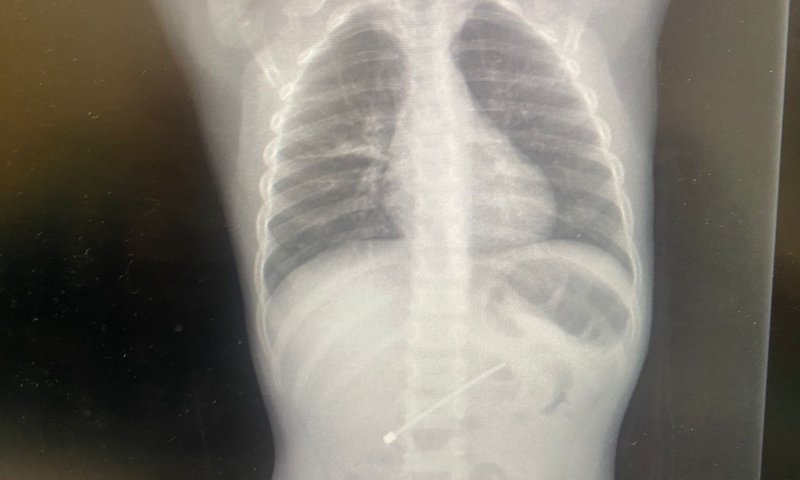

הבוקר בוצעה פעולה נוספת, לשליפת עצם זר לא שכיח – אנטנה של מכשיר אלקטרוני באורך של 7.5 ס"מ שנבלעה על ידי ילד כבן חמש מאזור הצפון. הילד, שהופנה לרמב"ם עם אבחנה ברורה, עבר לטיפולו של צוות המכון לגסטרואנטרולוגיה ותזונה לילדים, אשר שלף את העצם המסוכן מגופו תחת טשטוש.

"עצם שבנוי באופן הזה ונבלע, לא יכול היה לצאת מגוף הילד באופן טבעי מבלי לגרום לו לנזק מסכן חיים בדרך", אומרים במכון, "הליך פולשני לשליפת העצם באופן מבוקר, היה הכרחי". בפעולה הזו, שהייתה מעט יותר מורכבת, לקחו מספר אנשי צוות, ובראשם ד"ר ג'מאל גרה, רופא בכיר במכון. ההליך הסתיים בהצלחה והילד צפוי להשתחרר לביתו בקרוב.